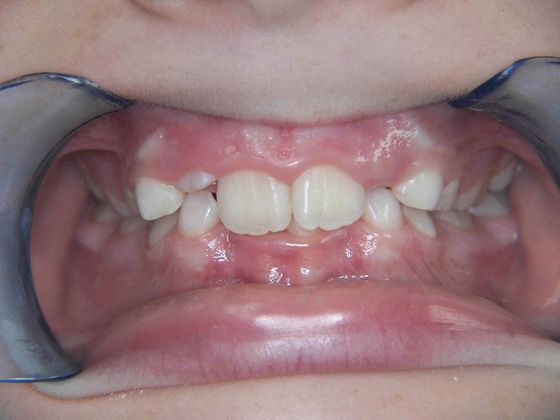

Orthodontics: Case 2

Patient is 9 years old and presents with 100% overbite and blocked out upper and lower lateral incisors. Both upper central incisors are palatally inclined causing a lack of space available for most anterior teeth. Advised her parents that she needs Phase I Interceptive Orthodontic treatment to provide room for all upper and lower front teeth. Phase I treatment was begun and finished, then began Phase II treatment shortly thereafter to finalize case. Removable retainer were fabricated for retention.